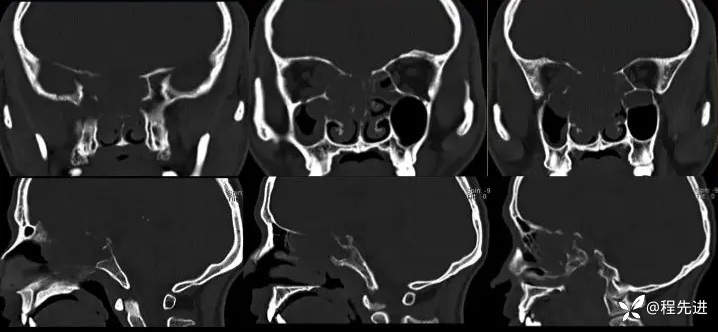

CT:

img